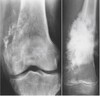

What pathology is seen here?

Osteoarthritis (OA) (look for the four radiographic signs)

181

Osteoarthritis (no picture frame appearance associated with OA)

182

OA